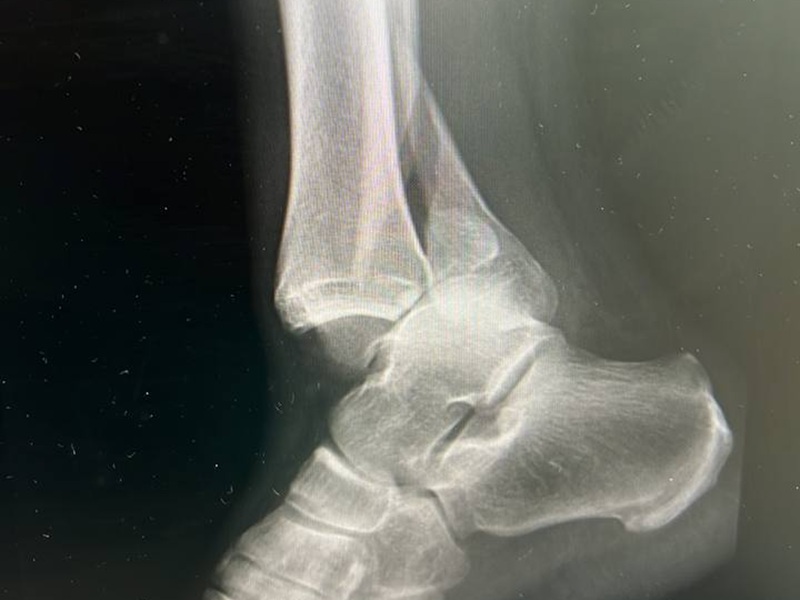

- переломы костей, трещины, последствия травм;

- признаки остеоартроза — сужение суставной щели, остеофиты;

Чаще всего исследуют коленные, тазобедренные, плечевые, локтевые, голеностопные суставы и суставы кисти. Это связано с частотой травм и нагрузками на эти зоны. Также рентген делают для контроля состояния после протезирования или при артрозе.

Рентген не дает полной картины, но может указать на косвенные признаки, например, накопление жидкости, изменение формы сустава, смещение костей. Для детальной оценки используют МРТ или УЗИ.